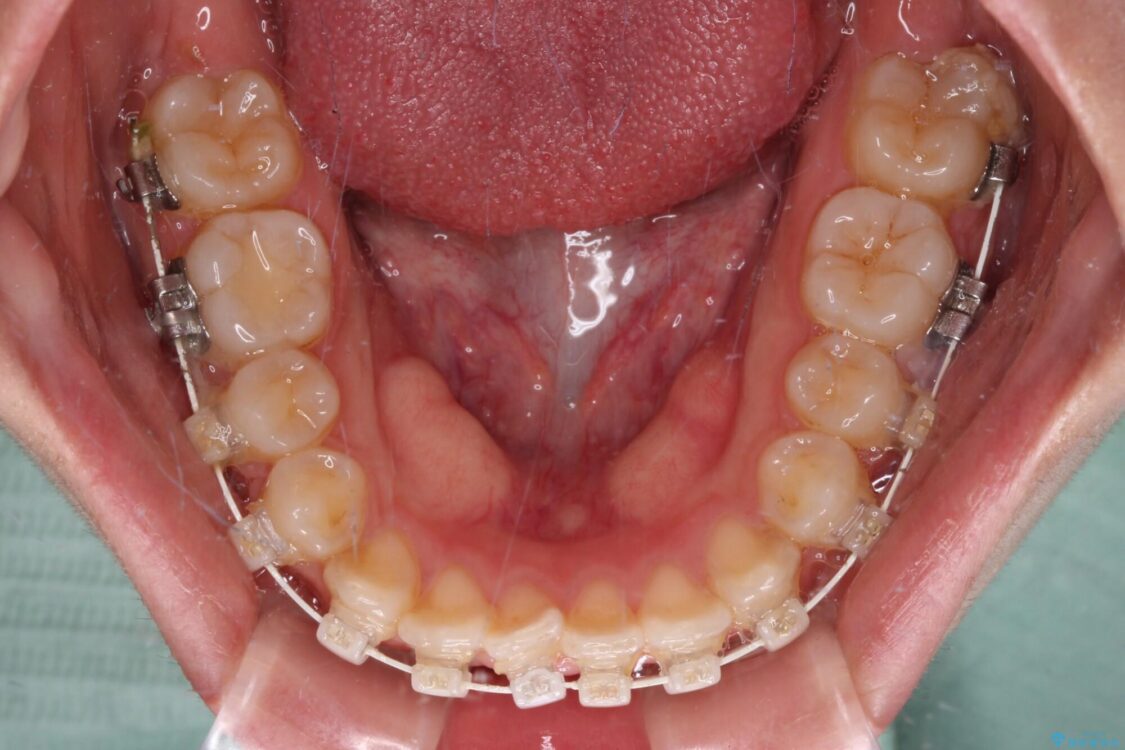

矯正装置

審美装置

マウスピース矯正のような自己管理の煩わしさは避け、早く治療を終えたいとのことで、ワイヤー装置による矯正治療を行うこととしました。

治療途中

• 【モニター】短期間で終わりたい ワイヤー装置での非抜歯矯正 治療途中画像